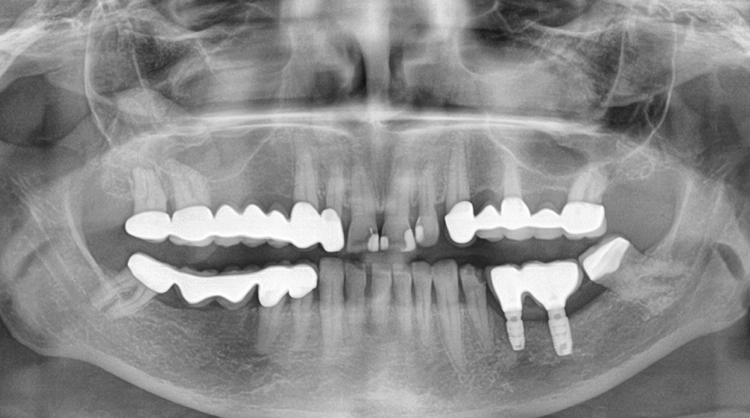

Die Verschraubung stellt eine wichtige Prävention gegen das Auftreten einer Periimplantitis dar. Das röntgenologische Abschlussfoto zeigt die knöcherne Regeneration des Defektes und gute Osseointegration der Implantate (Abb. 21).